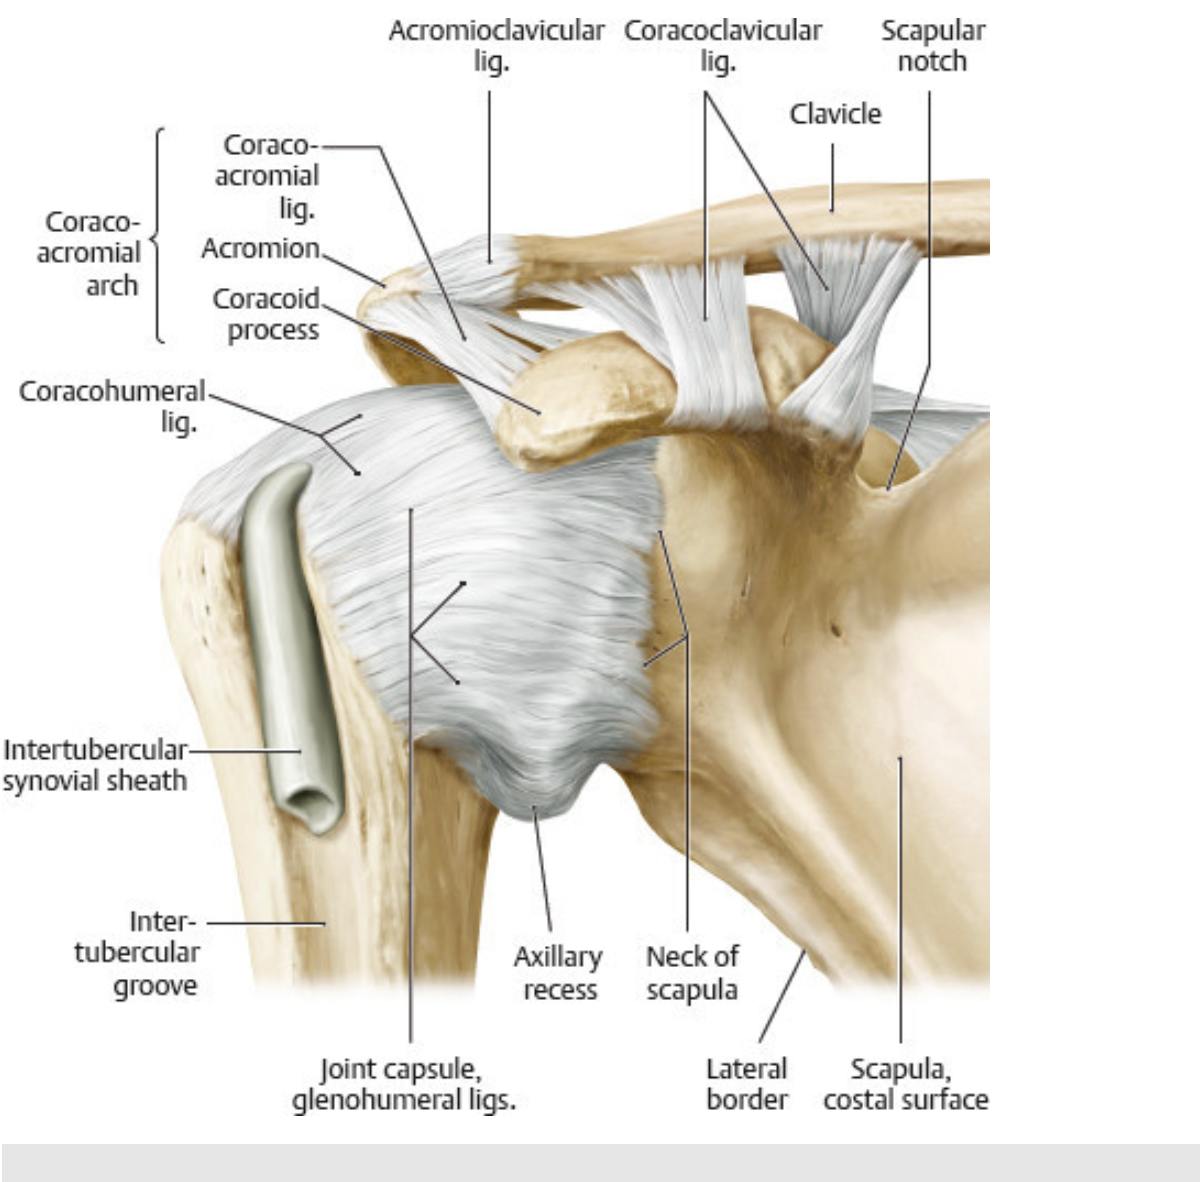

Note that the shoulder illustrates an important physical feature of joints in general - mobility and stability are mutually exclusive. In order to allow substantial mobility in the shoulder (consider the motions possible), the joint is vulnerable to instability (separation at the acromioclavicular joint that might involve dislocation (subluxation) at the glenohumeral joint).

Anterior view. The acromioclavicular joint is a ___ joint. Because the articulating surfaces are flat, they must be held in place by strong ligaments, greatly limiting the mobility of the joint.

Anterior view. The acromioclavicular joint is a plane joint. Because the articulating surfaces are flat, they must be held in place by strong ligaments, greatly limiting the mobility of the joint.

The ___ joint is the most mobile but least stable joint of the body, and dislocations are frequent. __ ___ muscles provide the greatest stability, supporting the joint anteriorly, posteriorly, and superiorly, but inferior support is lacking.

he glenohumeral joint is the most mobile but least stable joint of the body, and dislocations are frequent. Rotator cuff muscles provide the greatest stability, supporting the joint anteriorly, posteriorly, and superiorly, but inferior support is lacking.

Anteriorly, the subtendinous bursa of the subscapularis, which lies between the tendon of the subscapularis and the neck of the scapula, communicates with the synovial cavity of the joint.

Superiorly, the subacromial bursa lies under the coracoacromial ligament and above the supraspinatus tendon and glenohumeral joint capsule.

Laterally, the Subdeltoid bursa a lies deep to the deltoid muscle and above the subscapularis tendon. It communicates with the subacromial bursa.

The ___ ligament between the coracoid process and acromion prevents superior dislocation of the humerus from the glenohumeal joint .

The coracoacromial ligament between the coracoid process and acromion prevents superior dislocation of the humerus.